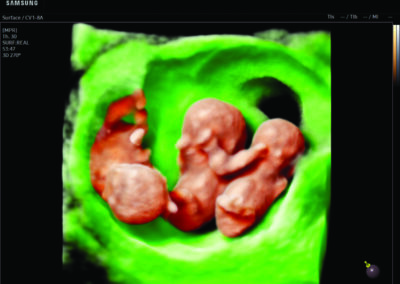

- Multiple births